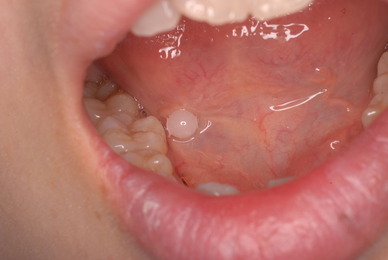

²¼³Ü²£¸þ¤¤Î¿ÆÉÔÃΤòºòÆüÈ´»õ¤·¤¿Êý¤ÎËÜÆü¤Î¾õÂ֤Ǥ¹¡£

°ì±þÌô¡Ê¾Ã±êÄÃÄ˺ޡˤò½Ð¤·¤Æ¤¤¤Þ¤·¤¿¤¬¡¢°ìγ¤â»ÈÍѤ·¤Æ¤¤¤Þ¤»¤ó¡£

Äˤߤâ¼ð¤ì¤â¤Ê¤¤¾õÂ֤Ǥ¹¡£Ë¥¤Ã¤Æ¤¤¤Ê¤¤¤Î¤ÇÈ´¤¤¤¿½ê¤ÏϪ½Ð¤·¤Æ¤¤¤Þ¤¹¡£¤À¤«¤é¤³¤½¼ð¤ì¤Ê¤¤¤Î¤Ç¤¹¤Í¡£Ë¥¹ç¤¹¤ë¤ÈÆâ½Ð·ì¤·¤Æ¼ð¤ì¤ë¤Î¤Ç¤¹¡£

»Äǰ¤Ê¤³¤È¤Ë½ý¸ý¤Ï³«¤¤¤Æ¤¤¤Þ¤·¤¿¡£